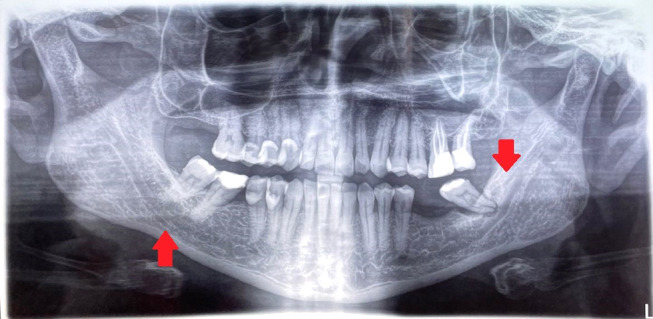

背景/目的:下颌骨管(MC)的解剖已经在文献中被广泛描述。许多研究对其解剖变异和异常进行了研究。多年来,人们使用了不同的方法来研究下颌骨,并提出了不同的分类方法。患者和方法:进行文献检索,以确定有关下颌管,双裂和三裂下颌管的文章。这项搜索使用了PUBMED和WoS计算机数据库,时间从1931年到2023年。不属于检索范围的研究被排除在外,例如那些摘要为初步评价提供的信息不足的研究。另外,一些没有被数据库检索到的文章,包括病原学方面的文章,是手工输入的。对于所有被认为符合条件的研究,检索并下载了文章全文。结果:根据文献分析,MC的变异可分为二裂MC、三裂MC、下颌内副管和牙管。下颌外颊管和舌管需要重点研究,因为它们非常频繁,数量众多,并且具有营养功能。结论:本文强调了MC变异的一些重要的放射学和解剖学方面,以及它们与实际分类的临床意义。有些分类仅具有统计和历史价值,对牙医和口腔外科医生没有实际用途。如果不能正确识别重复可能会导致围手术期并发症。需要对MC的前、中、后三个部位的不同变化进行新的研究。提出了一种更有用的分类方法。

Results: Based on the analysis of the literature, the variants of the MC should be classified as bifid MC, trifid MC, intramandibular accessory canals and dental canals. Extramandibular buccal and lingual canals require focused research, because they are very frequent, numerous, and they have nutrient functions.

Conclusion: This article highlights some important radiological and anatomic aspects regarding variations of the MC and their clinical implications in relation to their actual classification. Some classifications have only statistical and historical value without real utility for dentists and oral surgeons. The presence of duplications may cause perioperative complications if they are not correctly recognized. New studies should be conducted on the different variations of MC in its anterior, middle and posterior. A more useful classification is proposed.